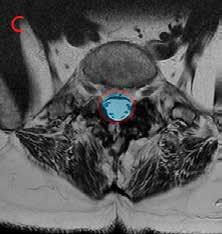

väliin (kuva 1B). Ylirasitus on siten tavallisin syy tämän tyyppiselle nikamasiirtymälle, jota tavataan usein nuorilla urheilijoilla ja tanssijoilla. Siirtymän syntyyn vaikuttaa kuitenkin myös huonosti ymmärretty perimän kautta välittyvä alttius eli joskus siirtymä voi syntyä vaikka minkäänlaista ylirasitushistoriaa ei olisikaan. Siirtymä ei kuitenkaan ole perinnöllinen sairaus eikä sitä ole koskaan kuvattu vastasyntyneellä.

Kuva 1. Magneettikuvat lannerangasta seisovassa asennossa sivusuunnasta katsottuna. Kuvassa A näkyy L4-nikaman kulumaperäinen siirtymä eteenpäin (nuoli). Välilevy nikamasiirtymän kohdalla on madaltunut kulumamuutoksena. Kuvassa B näkyy rasitusmurtuman pohjalta syntynyt nikamasiirtymä L5-nikamassa (nuoli). Myös tässä siirtymävälin välilevy on madaltunut kuluman seurauksena.

Rasitusmurtumaperäisessä nikamasiirtymässä vain nikaman runko-osa siirtyy eteenpäin, mutta nikamasta rasitusmurtuman seurauksena irti jääneet takakaaret jäävät paikoilleen. Keskeinen selkäydinkanava ei tässä tilanteessa ahtaudu ja ahtaumaoireiden ilmestyminen on epätavallista (kuva 2). Oireilu onkin tyypillisesti siirtymävälin epätukevuuteen palautuvaa selkäkipua ja selän epätukevuusoireilua. Siirtymävälin kuluessa välilevy madaltuu ja tässäkin siirtymätyypissä usein tavataan hermopinneoireilua, joka syntyy L5-hermojuuren jäädessä pinteeseen ahtaassa hermojuurikanavassa.

Kuva 2. Magneettikuvat poikkileikkeinä selällään makaavasta henkilöstä. Selkäydinkanavan pinta-ala on merkitty kuviin läpikuultavalla varjostuksella punaisen ääriviivan sisällä. Kuvassa A nähdään voimakasasteinen selkäydinkanavan ahtaus L4/5-välissä. Kyse on samasta henkilöstä kuin kuvassa 1A. Kuvassa B näkyy nuoren henkilön normaalilaajuinen selkäydinkanava L4/5-välissä.

Kuvassa C nähdään normaalilaajuinen selkäydinkanava rasitusmurtumaperäisen siirtymän kohdalla välissä L5/S1. Kyse on samasta henkilöstä kuin kuvassa 1B.